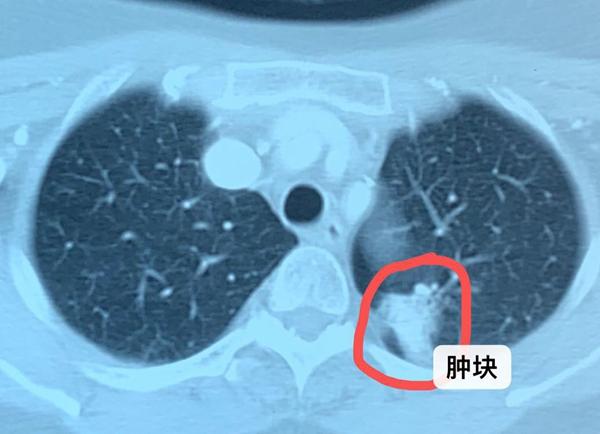

从临床发现,约70%的肺癌,一旦发现就已经是晚期。这主要是由于肺癌没有特异性的临床表现和典型的症状,往往症状病比较重视才会被发现。咳嗽、咳痰、咳血是肺癌的临床表现。

引起肺癌咳血原因主要是由于肿瘤压迫和侵犯的气管和肺组织由于肿瘤的侵蚀作用造成了肺内的血管或者毛细血管的破坏,就会引起出血,在咳嗽时就会出现痰中带血,甚至直接由于出血造成咳嗽咳出血或者血凝块。

一旦发生咳血,往往意味着肿瘤比较大或者肿瘤的位置接近大的气道,因此,一定要及时就医,及时治疗。